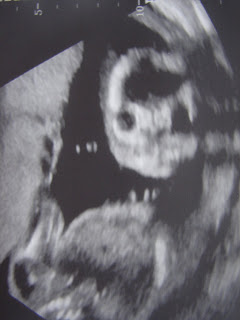

You know how it goes. You have a prenatal appointment, they do an ultrasound, they let you see your baby, and you’re just filled – suffused – with the joy of seeing your beautiful baby boy right there on the screen, every healthy – healthy! – bouncing inch of him, little legs bending and kicking (oooh, my goodness, you have a little active one! says the radiologist), little hand shoved in little mouth, and you think, that’s my baby, that’s my beautiful baby.

And the radiologist says, I just need to get a look face-on, and pushes and prods at your belly with the ultrasound stick, and then exclaims, oh, look, there’s the little face!

And you think, oh, my. SKELETOR.

But he’s still the most beautiful boy that you’ve ever seen.